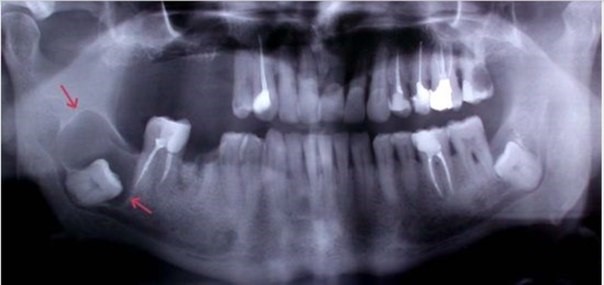

Новообразования также могут возникать и в мягких тканях, и в костной ткани челюстей, которые выявляются, как правило, при проведении рентгенологического обследования.

Любые новообразования в полости рта, обнаруживаемые самостоятельно пациентом или на приеме у стоматолога, а также выявляемые на снимках, требуют тщательной и внимательной оценки и обследования специалистом для принятия решения о необходимости лечения и выборе тактики лечения в конкретной ситуации.